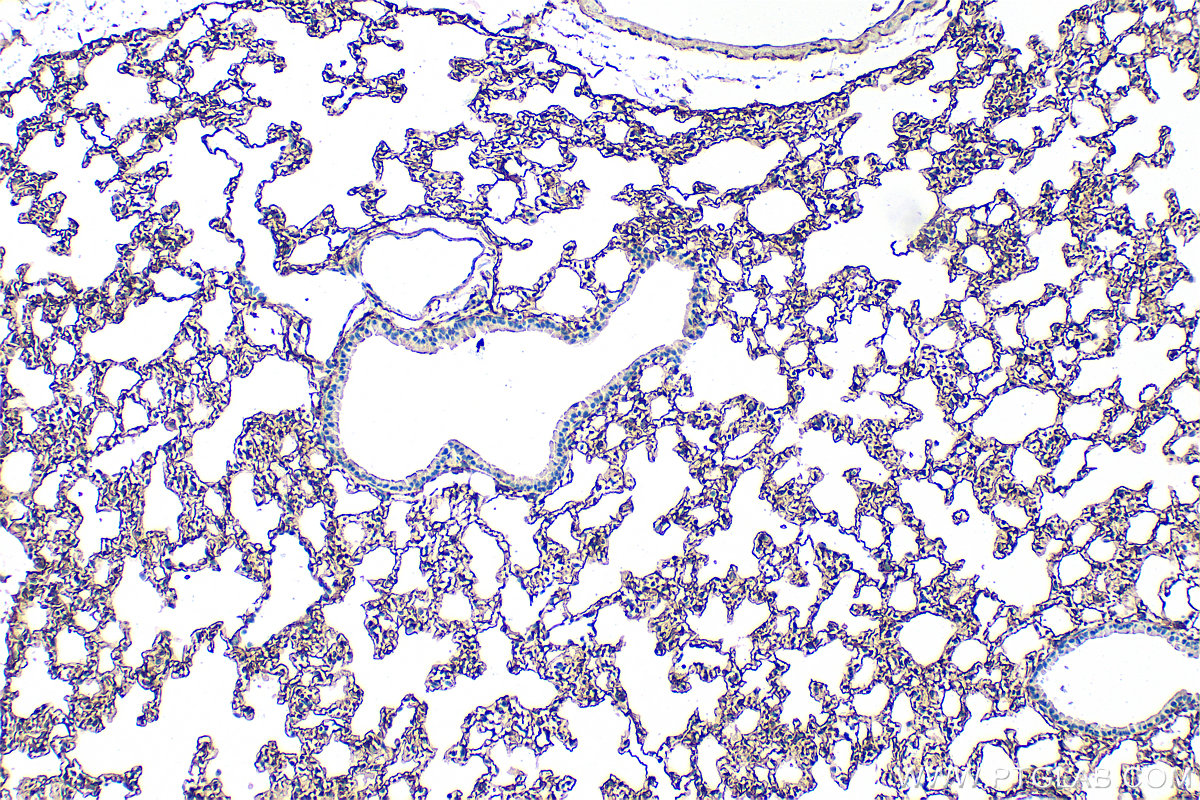

| Positive IHC detected in | mouse lung tissue, mouse kidney tissue Note: suggested antigen retrieval with TE buffer pH 9.0; (*) Alternatively, antigen retrieval may be performed with citrate buffer pH 6.0 |

| Immunohistochemistry (IHC) | IHC : 1:400-1:1600 |

33099-1-AP targets Podoplanin in WB, IHC, ELISA applications and shows reactivity with mouse samples.

Podoplanin was identified as a glycoprotein found in the cell membranes of glomerular epithelial cells (podocyte) (PMID: 9327748). It is a lymphatic marker because the expression of podoplanin has been detected in lymphatic but not blood vascular endothelium, and is useful as the marker of tumor-associated Lymphangiogenesis. Podoplanin has a function in developing testis, most likely at the level of cell-cell interactions among pre-meiotic germ cells and immature Sertoli cells. It may be involved in cell migration and/or actin cytoskeleton organization. When expressed in keratinocytes, PDPN induces changes in cell morphology with transfected cells showing an elongated shape, numerous membrane protrusions, major reorganization of the actin cytoskeleton, increased motility and decreased cell adhesion. It is required for normal lung cell proliferation and alveolus formation at birth. PDPN induces platelet aggregation. It does not have any effect on folic acid or amino acid transport and does not function as a water channel or as a regulator of aquaporin-type water channels.